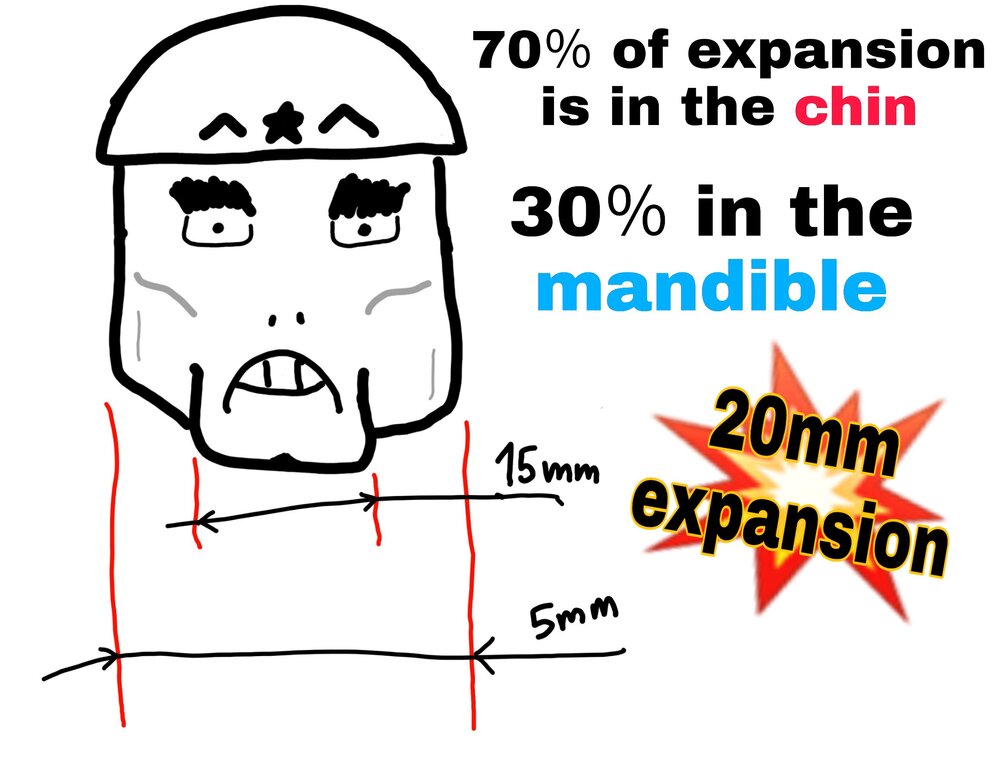

MSDO expands this much. This is from MSDO only:

Now for the sake of thread, let's imagine that you were about to expand 20mm (extreme case), usually your safe bet is to expand 5-10mm, but when MSE is done simultaneously with MSDO, there wouldn't be much to rish about, other than bite correction.

You should done MSDO together with MSE, because if you're spliting the bone and expanding it, then you're literally changing the angulation of your tempomandibular joint. You're probably gonna need a little orthodontic movement of the molars to get them to match perfectly if you're doing MSE with MSDO, because MSDO expands the front teeth more than the back teeths.

⚠ The key is to do MSE and MSDO at the exact same time with the exact same amount of expansion, because than not only the chin would be expanded outward, also the rest of the mandible and thus the condiles can move in their natural place with the expansion of the maxilla...

MSDO expands this much. This is from MSDO only:

It helped his midface, fwhr, and NCT a bit (wtf).Now for the sake of thread, let's imagine that you were about to expand 20mm (extreme case), usually your safe bet is to expand 5-10mm, but when MSE is done simultaneously with MSDO, there wouldn't be much to rish about, other than bite correction.

You should done MSDO together with MSE, because if you're spliting the bone and expanding it, then you're literally changing the angulation of your tempomandibular joint. You're probably gonna need a little orthodontic movement of the molars to get them to match perfectly if you're doing MSE with MSDO, because MSDO expands the front teeth more than the back teeths.

⚠ The key is to do MSE and MSDO at the exact same time with the exact same amount of expansion, because than not only the chin would be expanded outward, also the rest of the mandible and thus the condiles can move in their natural place with the expansion of the maxilla...